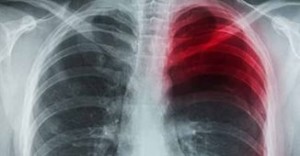

Самым опасным является то, если боль появляется непосредственно при вдохе. Причина может быть последствием невылеченной простудной болезни, которая переходит на более тяжёлую стадию заболевания. Из этого следует, что в лёгких развивается воспалительный процесс, который требует незамедлительного вмешательства. Боли в лёгких при вдохе могут значить развитие онкологических заболеваний (туберкулёз, ревматизм).

Ещё одним источником может служить образование злокачественных опухолей. В данном случае поражается защитная оболочка – плевра. В этот период появляется кашель и сильные, острые боли. Чаще всего, эти боли чувствуются в одном определённом участке грудной клетки.